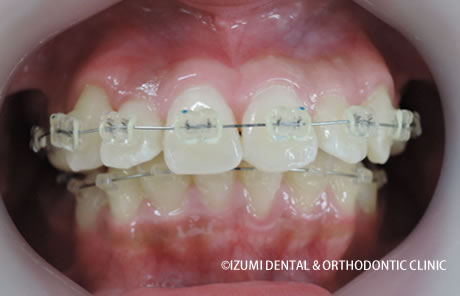

開始からヶ月後(歳 ヶ月)

そして、咬み合わせの高さを変えれば、歯は驚くほど自由に短期間に気持ちよく綺麗に並んでいくのです。

そして、なにより、症例を見ていただければお分かりになると思います。

正常な咬合高径(正常な咬み合わせ)を確保すると、歯槽骨や上下顎骨が、その方本来の形や大きさに変化していくので、健康な歯を抜かなくても、歯は綺麗に並んでいくのです。